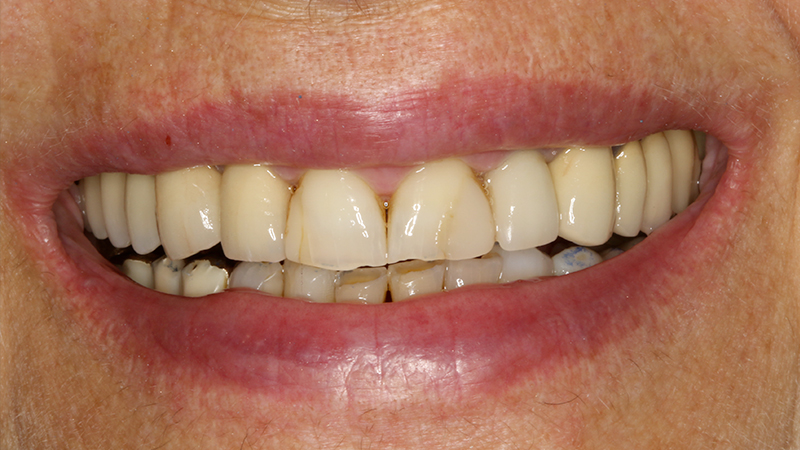

La paziente, di 68 anni, buona salute generale, presentava un grave problema al ponte 17-15-14 con dolore alla masticazione, mobilità e grave perdita ossea su 17 e 12 (Figs. 1, 2, 3).

La finalizzazione del caso avveniva con protesi in metallo-ceramica passivata su cappe conometriche in bocca (Figs. 24, 25, 26, 27, 28, 29, 30, 31, 32) e radiografie finali ad un anno dal carico (Figs. 33, 34).

Applicazione ponte 17-14 in metallo ceramica su cappette conometriche passivate in bocca mediante cemento

Fig. 24 - Applicazione ponte in metallo ceramica su cappette conometriche passivate in bocca mediante cemento Multilink Hybrid e risultato finale

Applicazione ponte 17 - 14 in metallo ceramica su cappette conometriche passivate in bocca mediante cemento Multilink Hybrid e risultato finale

Fig. 25 - Applicazione ponte 17 - 14 in metallo ceramica su cappette conometriche passivate in bocca mediante cemento Multilink Hybrid e risultato finale